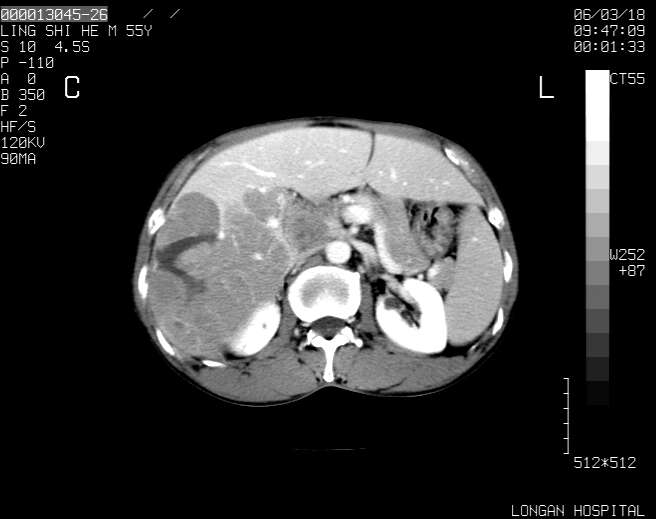

以下是引用guzhongliangddd在2006-3-21 22:13:00的发言:[br]病灶主要位于肝右叶的后份,内见异常血管,门脉主干及右支受侵{提示有癌栓形成},门腔间隙内见增大淋巴结。肝左叶内未见异常。

以下是引用zhuxinli在2006-3-22 1:23:00的发言:[br][br] 病灶主要位于肝右叶的后份,内见异常血管 .门脉右支截断,右叶前段早期强化(考虑动静脉漏),腹膜后肿大淋巴结,病灶逐渐强化,考虑为胆管细胞癌[br]